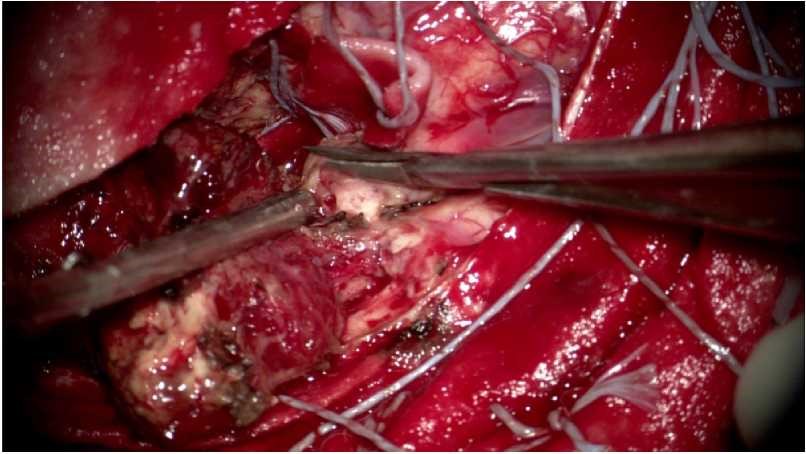

术中情况: